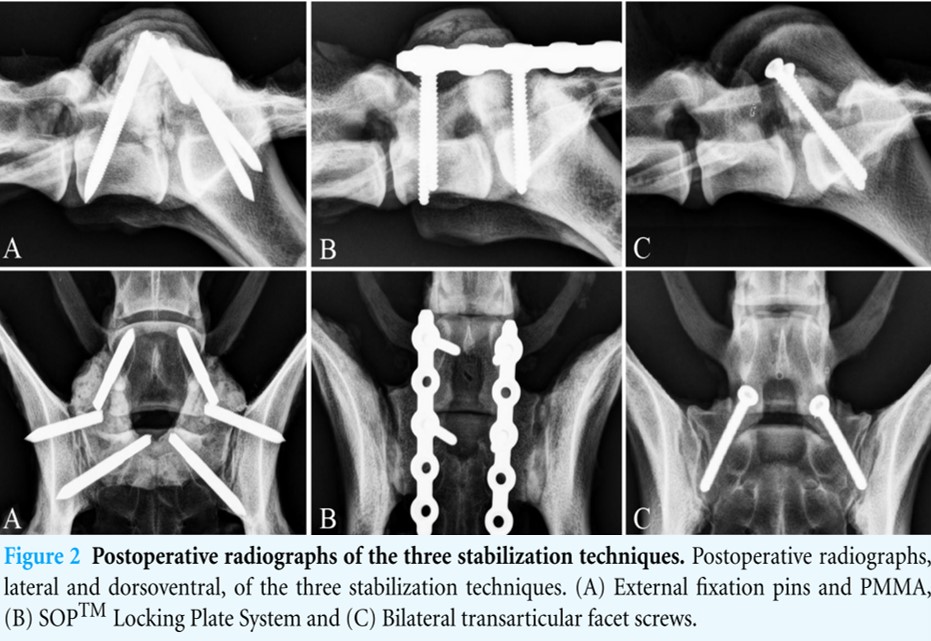

Gewindepins + Knochenzement

- Anmerkung Pinstärke Weh & Kraus (2007): 3,2 mm Pinstärke für Hund 54 kg evtl. zu wenig

- Infektionsrisiko Mensch bis zu 9,4% - wichtig: aseptische Technik, Prophylaktische AB, AB impregnierter PMMA (Weh & Kraus, 2007)

- dorsaler Zugang L7-S1

- dorsalen Laminektomie

- wird meist kombiniert

- Pinplatzierung L7

- Präparation zum Querfortsatz

- Vorbohrung

- im Winkel, wo der Proc. transversus zum Pedikel umschlägt

- 5-10° nach cranial

- 45° nach ventral

- Gewindepin platzieren

- Länge im vorhinnein am CT abmessen

- Pinplatzierung Sakrum

- Fasettengelenk freipräparieren

- direkt caudal vom Proc. articularis caudalis des L7 ins Sakrum bohren

- 45 ° nach ventral

- 45° nach caudal

- soll durchs Ilium gehen

- soll das Fasettengelenk zusätzlich sperren

- Pins verbinden

- Pins in die Mitte biegen

- mit Knochenzement verbinden

transartikuläre Fasettengelenksversteifung

- dorsaler Zugang

- dorsale Laminektomie möglich

- Eröffung der Gelenkskapsel der Fasettengelenke

- Entfernung Gelenksknorple mit Skalpel / Fräse

- Kortikalisschrauben 3,5 mm; 30-45°

Pedikelschraube & Platte

winkelstabile Verplattung